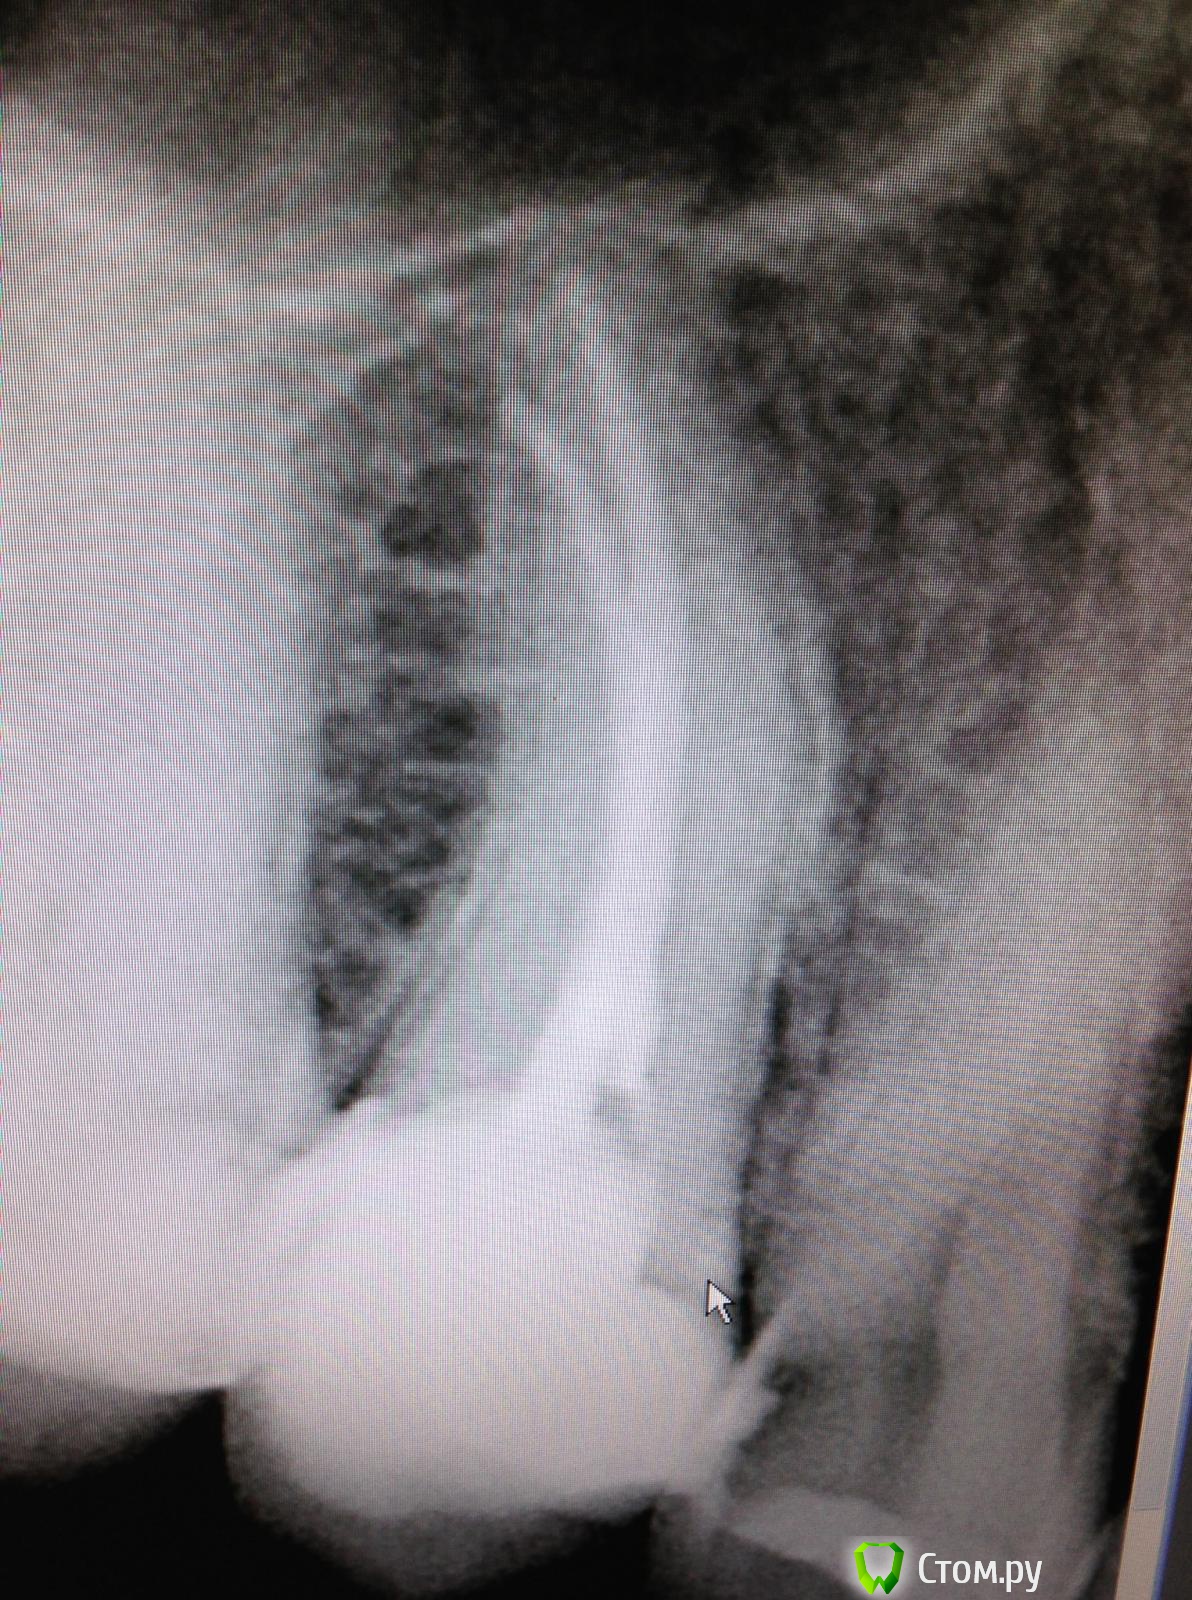

SSTi Опубликовано 19 июля, 2014 Автор Поделиться Опубликовано 19 июля, 2014 Зуб 27. Накрылся новапекс. Работа наощупь. Снимок после временной. Кто сколько каналов видит? 2 посещения искали 3 и 4 каналы. Не нашел Ссылка на комментарий

SSTi Опубликовано 19 июля, 2014 Автор Поделиться Опубликовано 19 июля, 2014 Топография устьев такая Ссылка на комментарий

Kolchanov Опубликовано 20 июля, 2014 Поделиться Опубликовано 20 июля, 2014 А эти сходились? Бывали двухканальные семерки. 1 Ссылка на комментарий

SSTi Опубликовано 20 июля, 2014 Автор Поделиться Опубликовано 20 июля, 2014 Эти не сходились. Два отдельных. Ссылка на комментарий